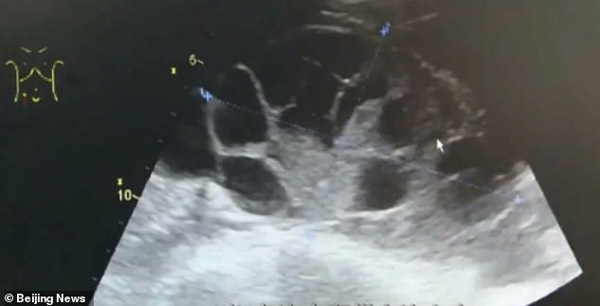

Ba ngày sau khi phẫu thuật, sức khỏe nữ sinh nhanh chóng xấu đi, cô bị đầy hơi nghiêm trọng, khó thở và nhanh chóng được đưa đến bệnh viện. Qua kết quả kiểm tra, nữ sinh được chẩn đoán mắc hội chứng quá kích buồng trứng, một tình trạng xảy ra khi buồng trứng trở nên quá kích thích do sự phát triển của trứng và chất lỏng tích tụ xung quanh.

Sau phẫu thuật hút trứng ra ngoài, buồng trứng của cô gái đã bị mở rộng như thể mang thai 7-8 tháng.

Cô gái trẻ được cho là đã tiêm hơn 10 mũi kích thích rụng trứng trước khi phẫu thuật lấy trứng. Các bác sĩ tiết lộ rằng hơn 5 lít chất lỏng đã được rút ra từ bụng của cô. Rõ ràng, buồng trứng của cô đã bị mở rộng như thể mang thai 7-8 tháng.